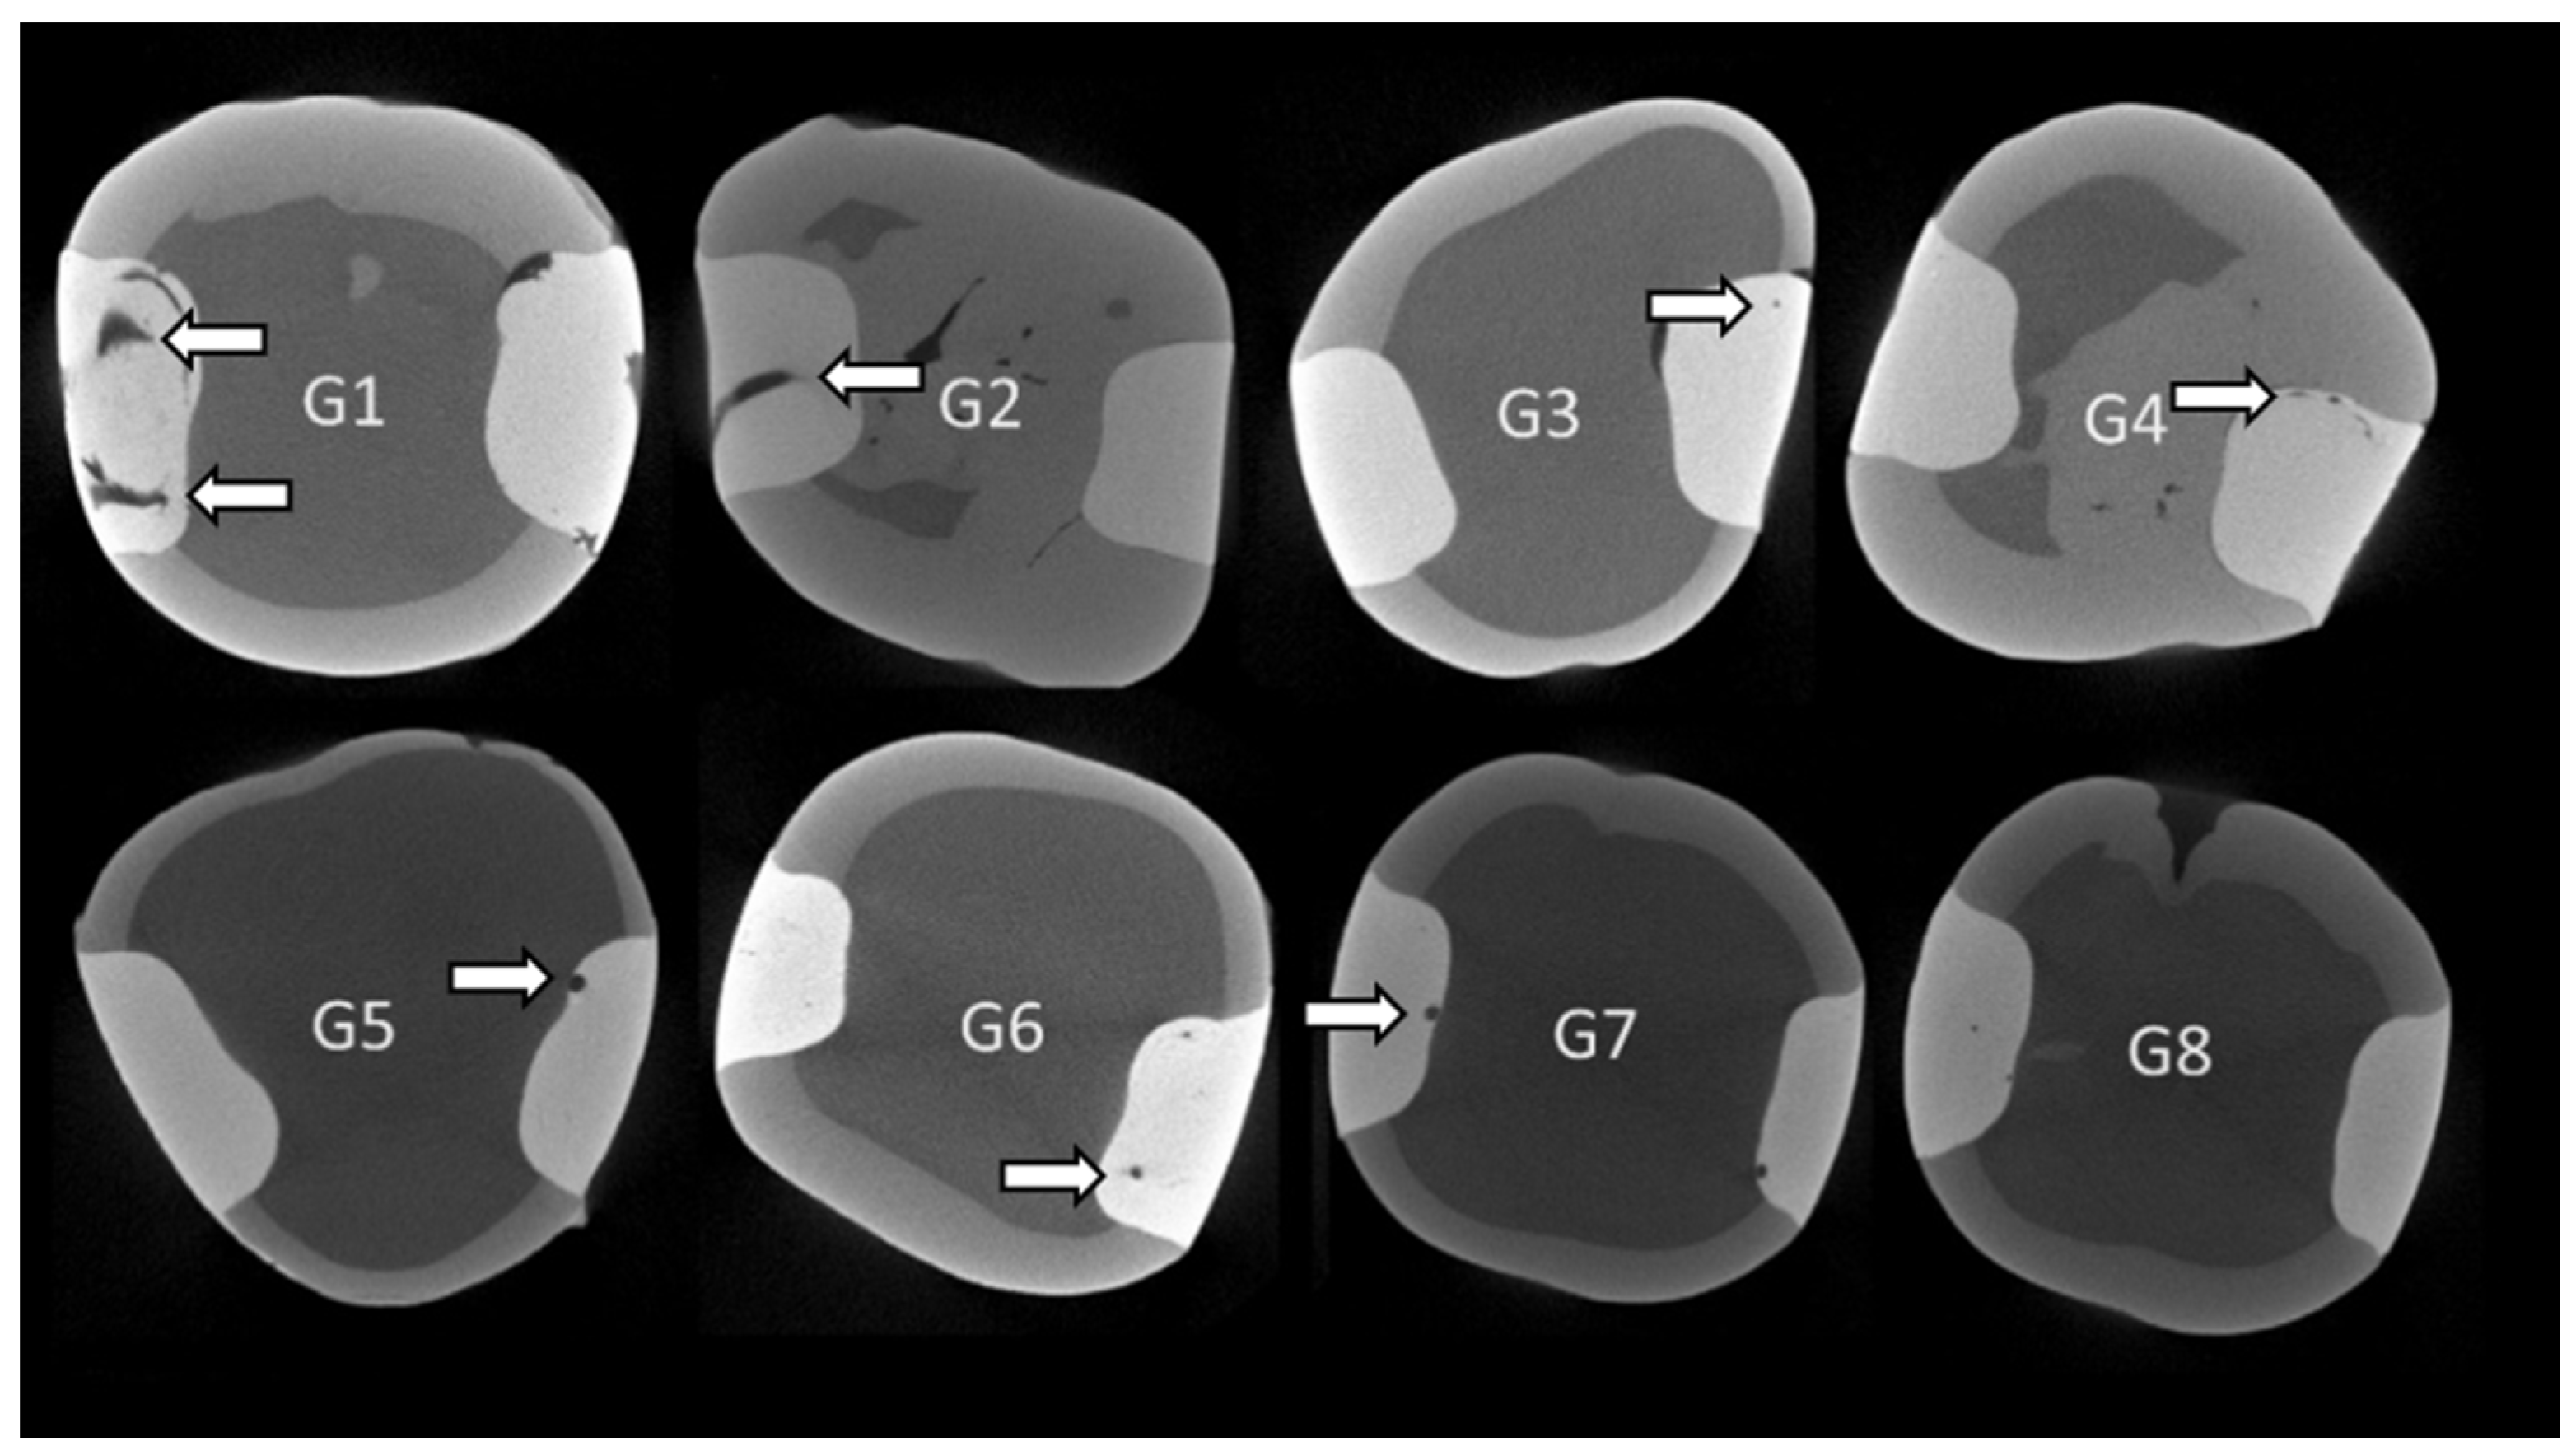

2.6. Void Analysis

3.1. Percentage (%) of Internal Voids